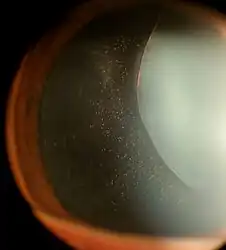

In Marfan syndrome, the health of the eye can be affected in many ways, but the principal change is partial lens dislocation, where the lens is shifted out of its normal position.[12] This occurs because of weakness in the ciliary zonules, the connective tissue strands which suspend the lens within the eye. The mutations responsible for Marfan syndrome weaken the zonules and cause them to stretch. The inferior zonules are most frequently stretched resulting in the lens shifting upwards and outwards, but it can shift in other directions as well. Nearsightedness (myopia), and blurred vision are common due to connective tissue defects in the eye. [13] Farsightedness can also result particularly if the lens is highly subluxated. Subluxation (partial dislocation) of the lens can be detected clinically in about 60% of people with Marfan syndrome by the use of a slit-lamp biomicroscope.[13] If the lens subluxation is subtle, then imaging with high-resolution ultrasound biomicroscopy might be used.

- Ectopia lentis in Marfan syndrome: Zonular fibers are seen.

- Lens dislocation in Marfan syndrome with the lens being kidney-shaped and resting against the ciliary body